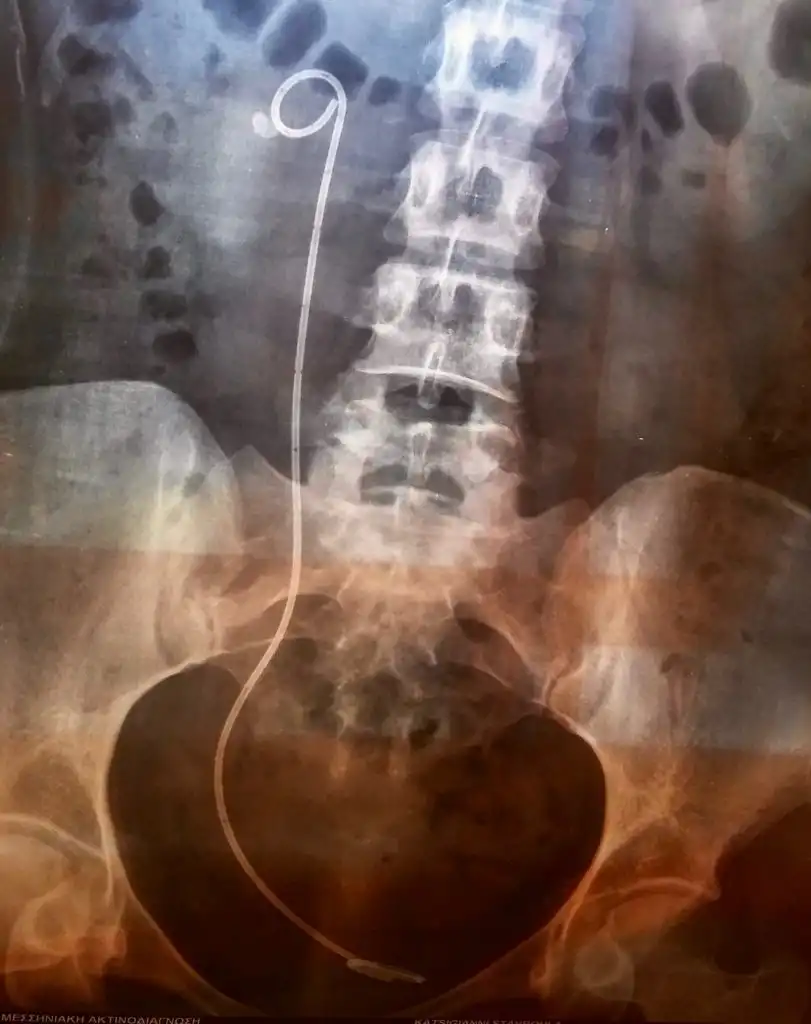

Ασθενής με ευμεγέθη λίθο στο άνω τριτημόριο του αριστερού ουρητήρα, ο οποίος φέρει νεφροστομία λόγω αποφρακτικής ουροπάθειας (Φωτογραφία 1), αντιμετωπίστηκε με laser ουρητηρολιθοθρυψία με ημιάκαμπτο ουρητηροσκόπιο και τοποθέτηση pig-tail με ταυτόχρονη αφαίρεση της νεφροστομίας (Φωτογραφία 2, 1η ημέρα μετεγχειρητικά). Η τρίτη φωτογραφία είναι στις 15 ημέρες πριν την αφαίρεση του pig-tail.